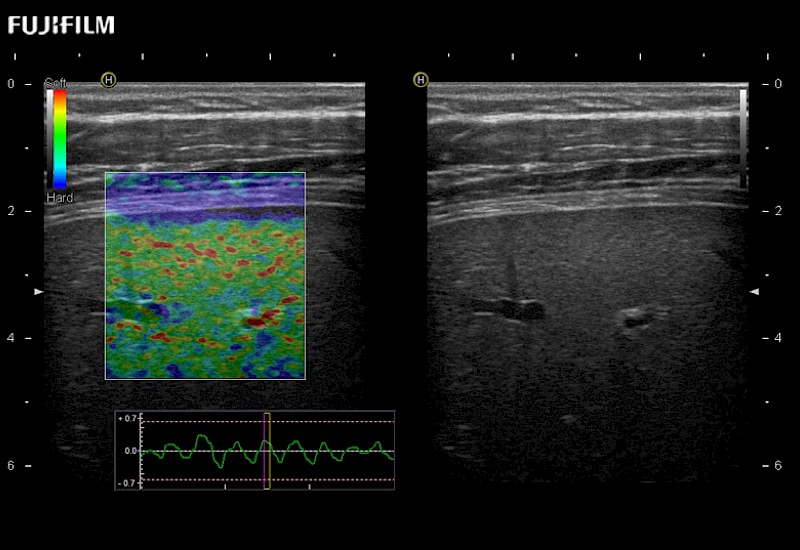

for use during general and laparoscopic procedures: Tumor localization & staging, Ablation, Resection, Biopsy, Transplant, Abdominal exploration, Robotic surgery

Our dedication to Laparoscopic Surgery allows us to offer superior image quality, outstanding system reliability and intuitive use of cutting edge technology.